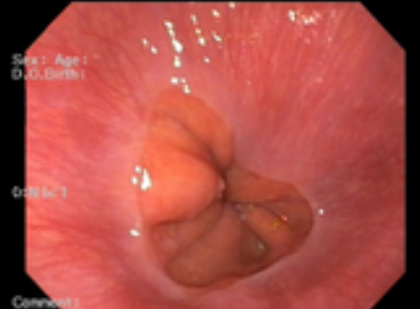

위내시경 검사 금식시간은 병원이나 방법에 따라 차이가 있을 수 있습니다. 위 안으로 내시경 카메라를 삽입해 식도와 위를 봐야 하기 때문에 음식물이 남아있으면 정확하게 검사하기가 어렵습니다.

위내시경 금식시간은 검사받는 시간 기준 최소 8시간은 아무 음식도 먹지 않고 금식해야 정확한 진단이 가능합니다. 미음이나 흰 죽 같은 유동식 음식을 드실 경우 위내시경 금식시간은 6시간 정도 지켜주면 됩니다. 보통 오전에 위내시경을 한다면 검사 전날인 저녁 8시 이후로는 음식 섭취를 제한하고 금식해야 합니다.

위내시경 검사받기 4시간 전에는 물(커피, 주스, 이온음료, 사탕 등)도 먹지 않는 것이 좋습니다. 참고로 껌은 먹다가 삼키는 것이 아니기 때문에 괜찮다는 의견이 있지만 일부 전문의는 금식해야 한다는 의견이 있으므로 피하는 것을 권장드립니다.

위내시경 검사를 앞두고 있다면 전날 식사에도 신경 써야 합니다. 짜거나 기름진 육류 위주 음식, 맵거나 자극적인 음식, 소화가 잘 안 되는 밀가루 음식은 피해야 하며, 흰 죽 같은 소화가 잘 되는 부드러운 음식을 먹는 것이 좋습니다.

특히 소주의 경우 위 점막을 자극해서 검사할 때 출혈이 발생할 수 있으므로 반드시 금주하기시 바랍니다. 특히 흡연의 경우 위 운동을 자극시켜 위액 분비를 촉진시킬 수 있어 검사에 방해가 되고, 불편감을 초래할 수 있기 때문에 반드시 금연하는 것이 좋습니다.